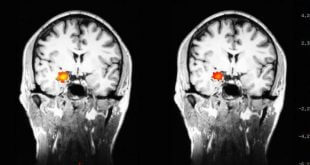

نوروسافاری | محققان در حال مطالعه این موضوع هستند که تغییرات در مغز بیماران مبتلا به افسردگی چگونه است. در سال ۲۰۱۵ تعداد ۱۶٫۱ میلیون آمریکایی تجربه ی افسردگی حاد خود را در سال قبل از آن گزارش داده اند به طوری که اغلب آن ها در عملکرد شخصیشان …